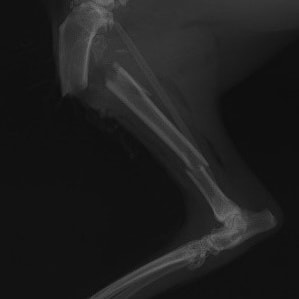

症例3:キルシュナーワイヤーのピンニングによる整復

ペルシャ猫 11ヶ月齢 雄

他院にて左大腿骨遠位の成長板骨折(salter-harrisⅠ型)が認められており、治療相談を目的として来院。当院にて、キルシュナーワイヤーを用いたピンニングにより骨折部位の整復を行いました。術後の経過は良好で、現在も経過観察中です。

術前レントゲン

術後レントゲン